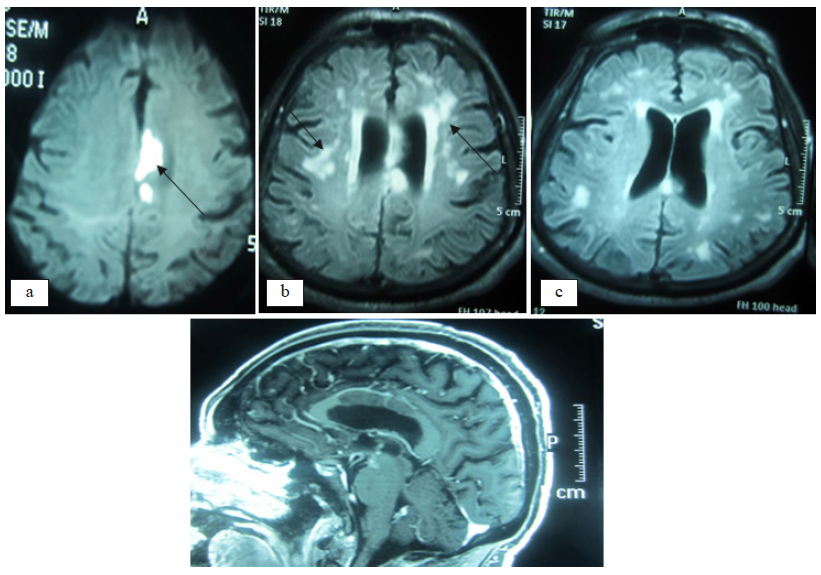

Investigación con neuroimágenes

Con el propósito de determinar el compromiso grave del estado neurológico del paciente, que explicara los severos defectos cognitivos, los trastornos comportamentales y los diferentes tipos de epilepsia que habían acaecido durante décadas del desarrollo de la enfermedad, se efectuaron estudios con tomografía cerebral, resonancia magnética del cerebro y estudio angiográfico del sistema carotídeo y vertebro-basilar. Figura 2

No existe la menor duda con respecto al diagnóstico de EB en ambas presentaciones, al referirnos a las manifestaciones aftosas, así como a las asociaciones con patología vascular autoinmune en los miembros inferiores. Los resultados en el LCR (pleocitosis linfocítica con proteinorraquia), igualmente los trastornos neurológicos encefálicos y medulares permiten conceptuar, en ambos casos, como afectos de NB. En el paciente varón la cefalea crónica, las diferentes formas de epilepsia, los trastornos progresivos de la función cognitiva hasta llegar a la demencia, la distimia depresiva, alternante con episodios de euforia, delirio paranoide, constituyeron las manifestaciones neurológicas y psiquiátricas que complementadas con los hallazgos en las neuroimágenes TEM y RMC, que muestran lesiones compatibles con angiopatía vascular isquémica crónica, constituyen el subgrupo parenquimatoso de la enfermedad (NB) (4), desarrollados en el lapso de 34 años. Debemos de precisar que los hallazgos en el líquido cefalorraquídeo y los de las neuroimágenes son similares a los descritos en la literatura.